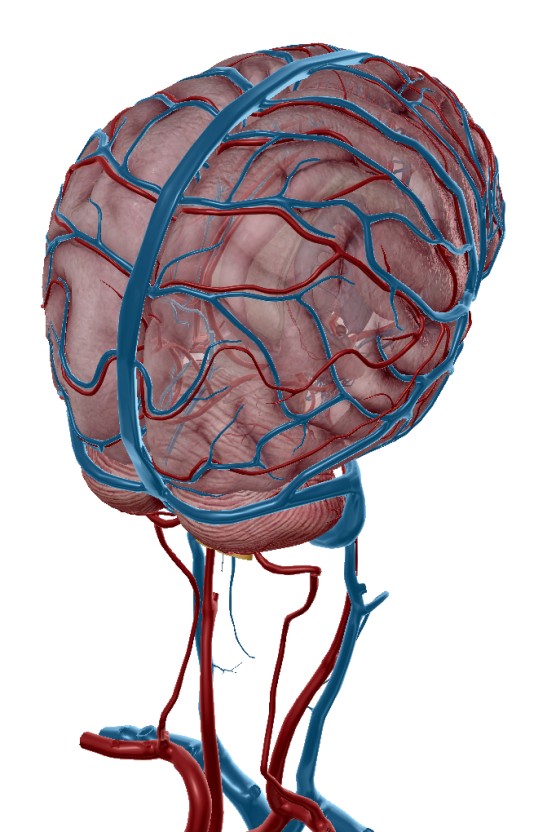

심장으로부터 뇌로 가는 혈류가 급격히 떨어지면 어지럼증, 균형 상실, 쓰러질 듯한 느낌이 올 수 있습니다.

이것이 심근경색의 신호라면, 다음은 실신 혹은 심정지로 이어질 수 있으니 매우 위험합니다.9. 불안감 및 죽음에 대한 공포